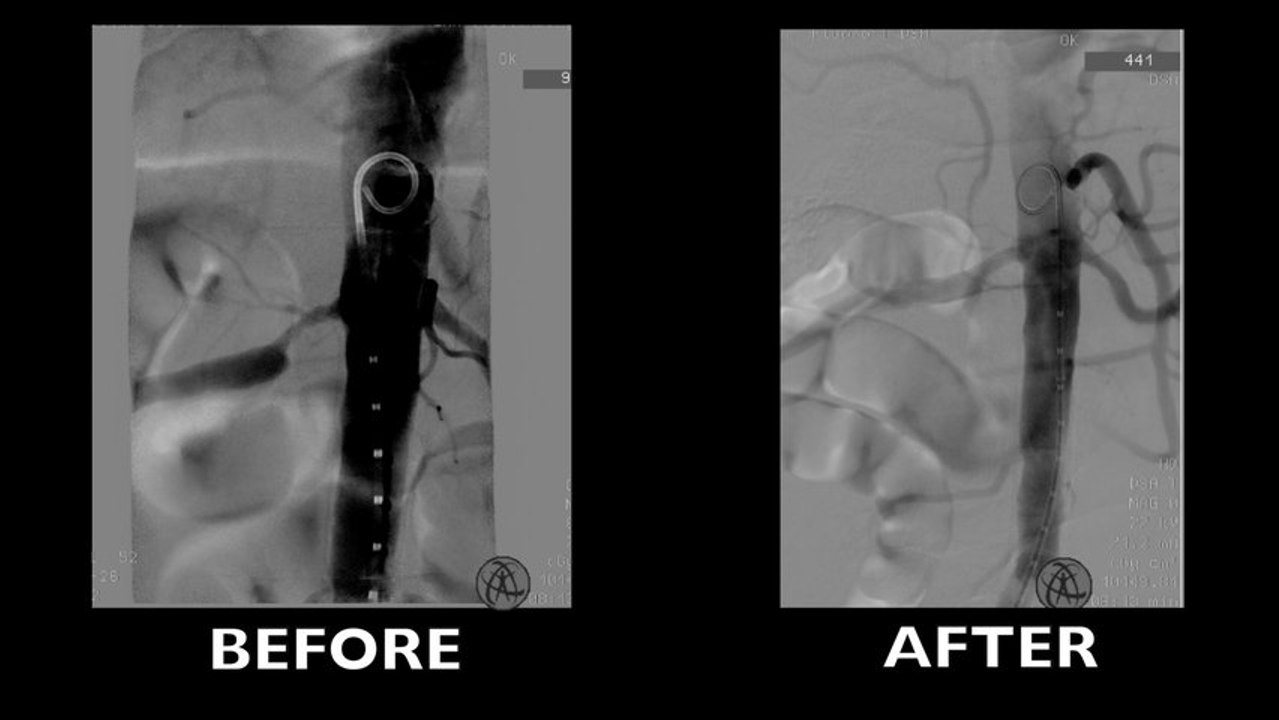

The mobile hybrid room solution

Live cases from Antwerp (Belgium)